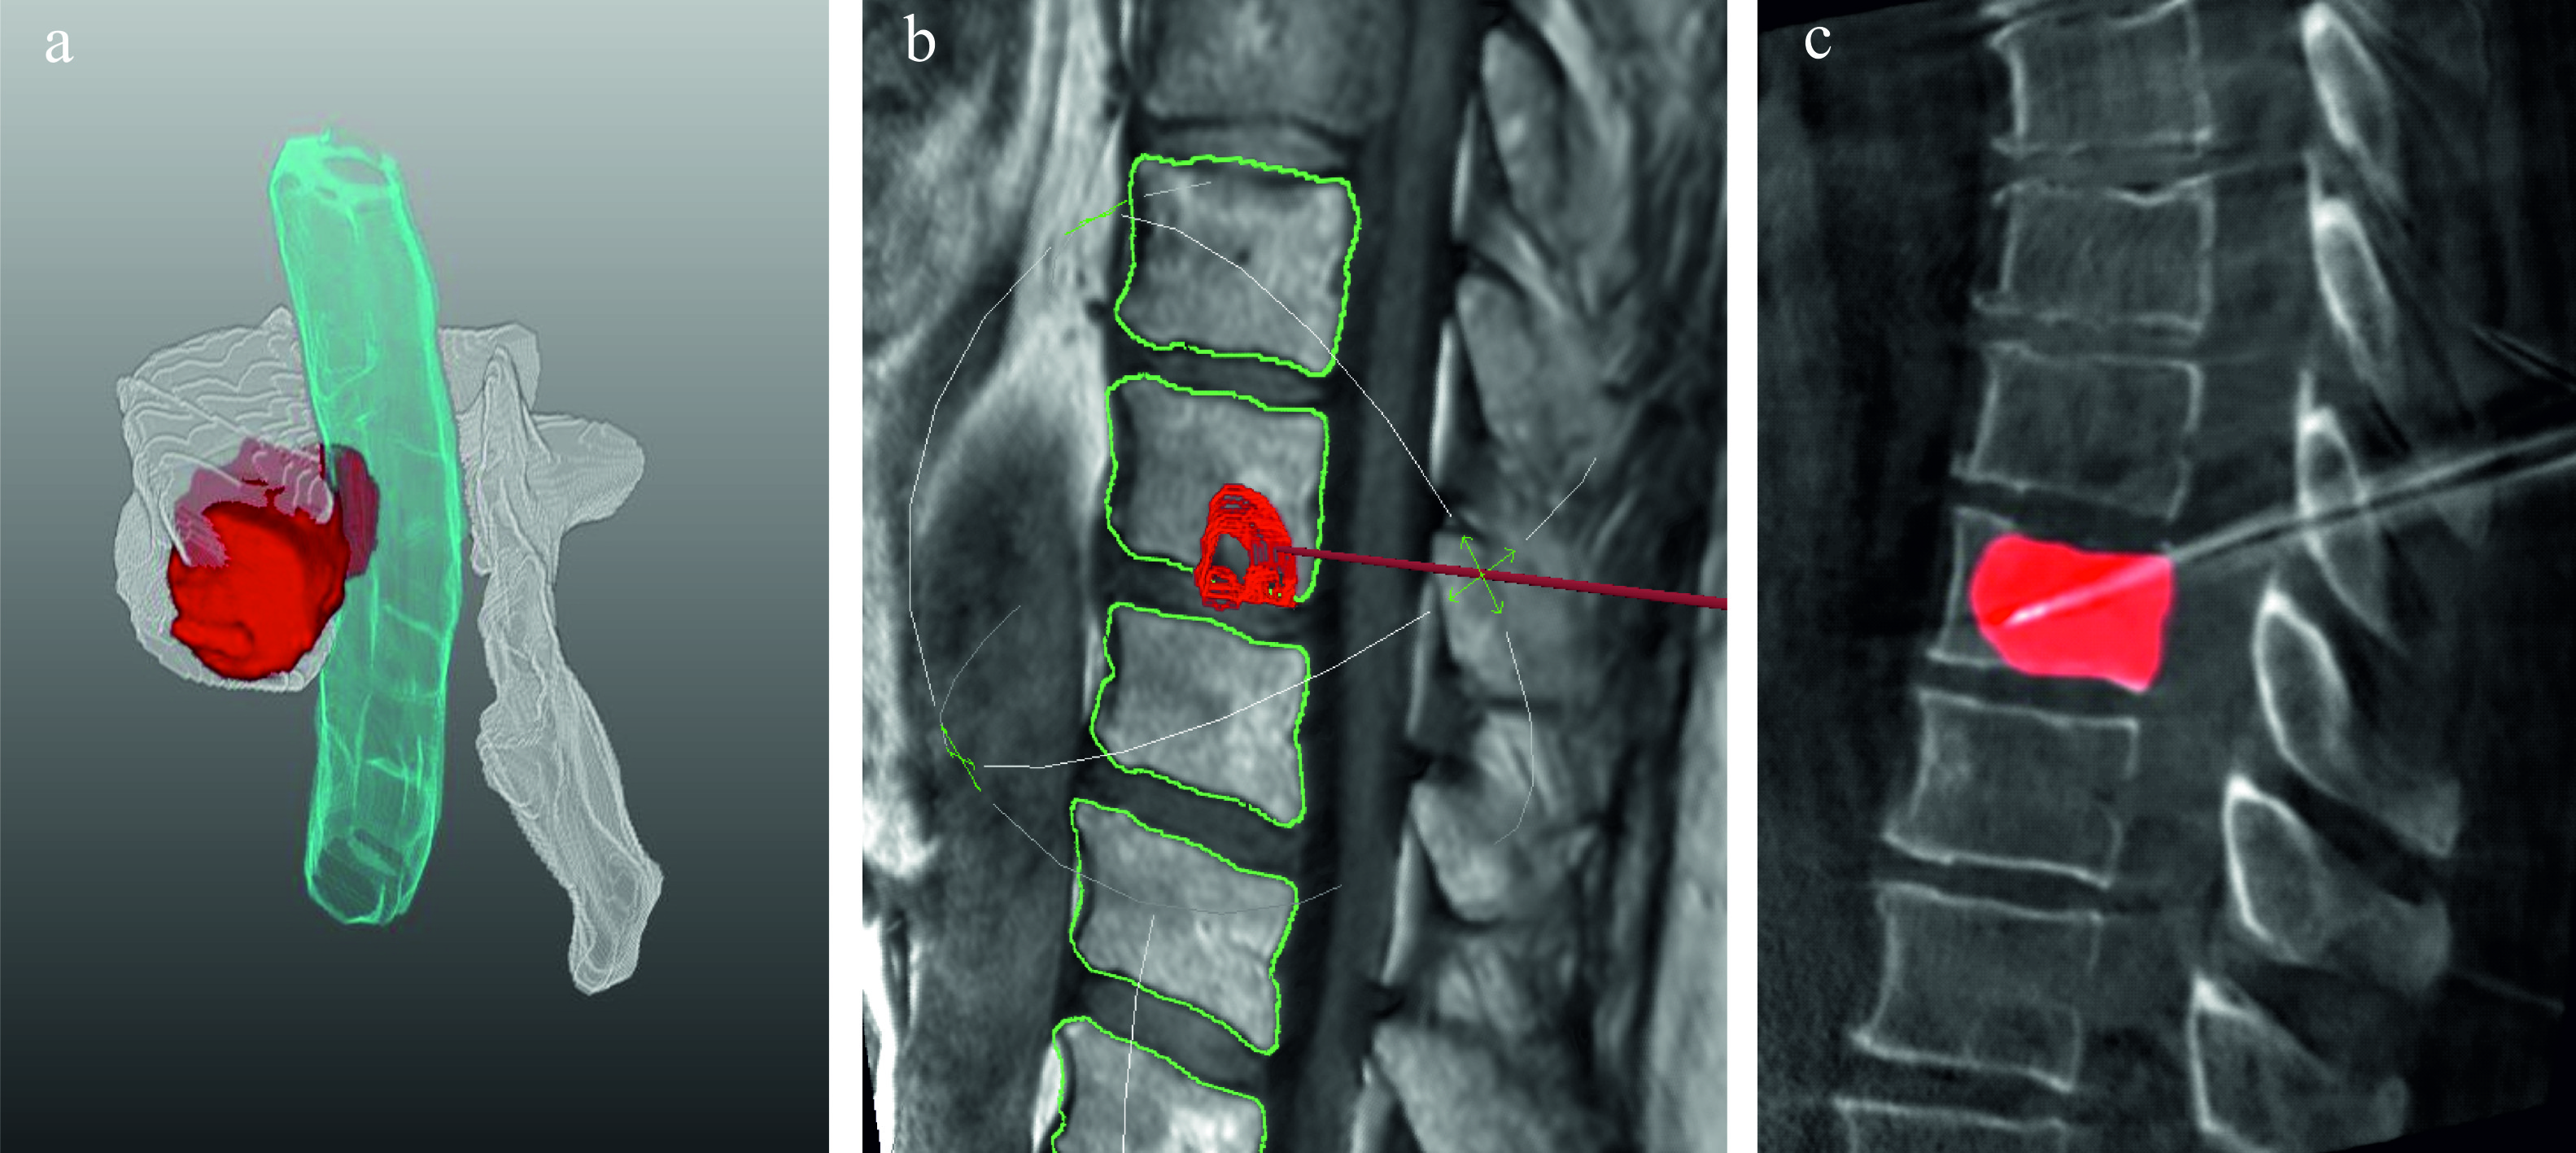

With regard to minimally invasive image-guided interventions like radiofrequency ablation (RFA), the segmentation of vertebral metastases constitutes an essential prerequisite for various workflow steps, starting from therapy planning, over the intervention procedure, up to the treatment outcome validation (see Fig. 2). First of all, it enables a detailed assessment of extent, shape and spatial relations of the metastases with surrounding risk structures and thus supports the planning of access pathways and positioning of minimally invasive applicators. In addition, patient-individual simulations of RFAs, i.e. ablation zone predictions are based on these segmentations weihusen2010towards ; kroger2006numerical . Pre-interventionally produced segmentation masks used as overlays onto the intra-operative images can enhance navigation w.r.t. accuracy and time required for metastasis puncturing and therefore, have a beneficial effect on the treatment outcome. Finally, after image registration of pre- and post-operative MRI scans, quantitative outcome validations are made feasible by matching the segmentation masks of metastases and necrosis zones. A computer-assisted approach could save time during routines and recurrent procedures and relieve the workload of radiologists, since segmentation of volumetric image data is time-consuming and fatiguing given the large number of image slices and sequences acquired per patient.